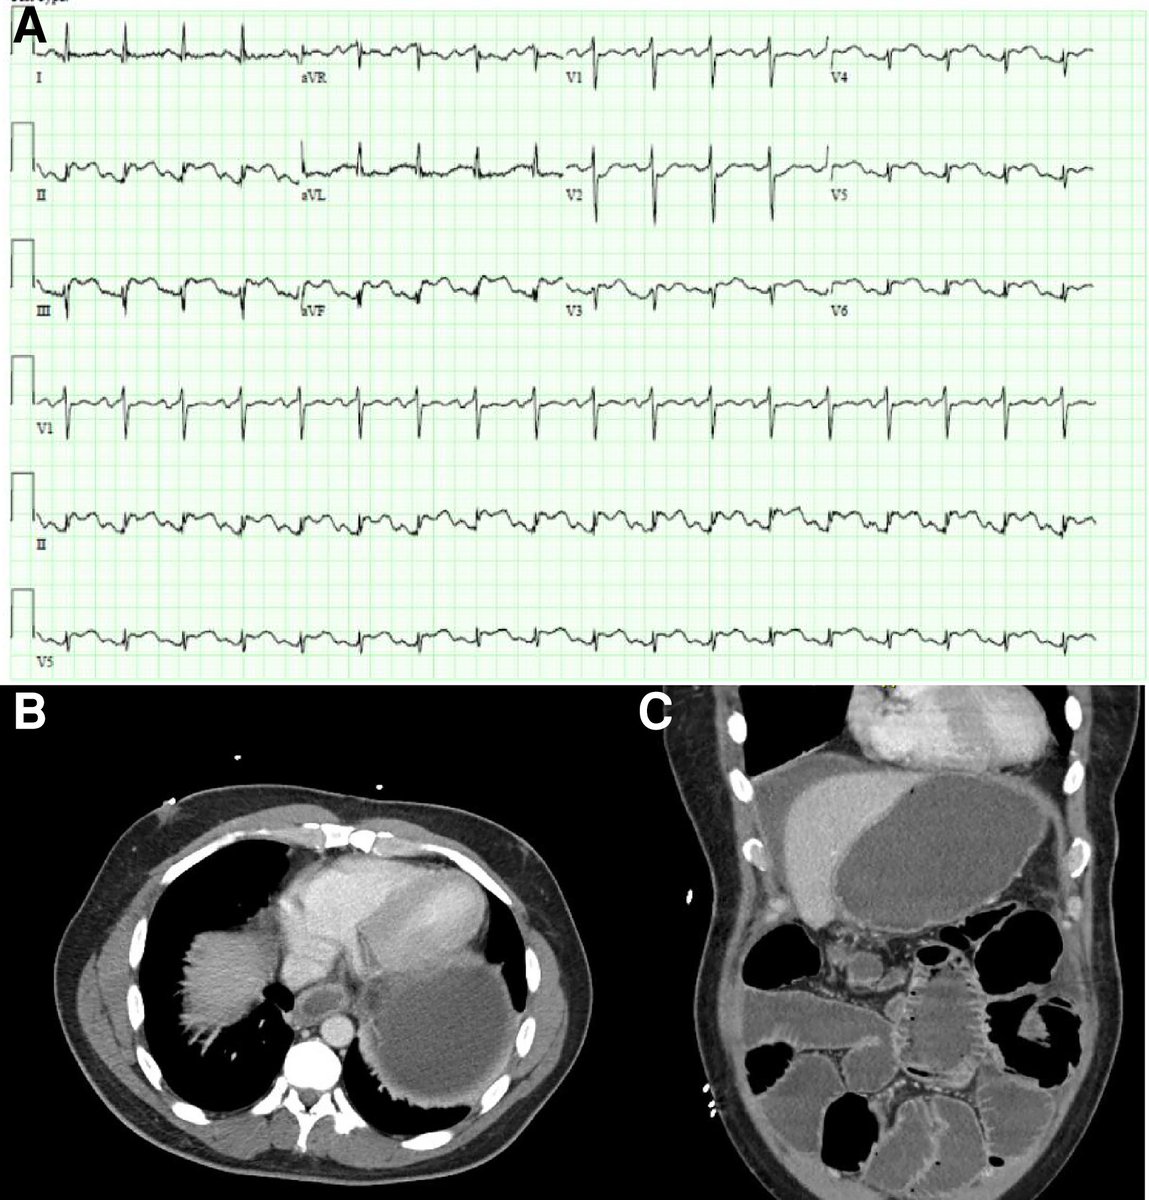

New #SpotTheDiagnosis is out Check out the case in #EHJACVC 👉doi.org/10.1093/ehjacc… What caused ECG changes? 👇 1. Acute plaque rupture in mid RCA 2. Viral pericarditis 3. Pericardial irritation from inflammation 4. PE in setting of recent surgery EHJACVC Editor-in-Chief Milica Aleksic